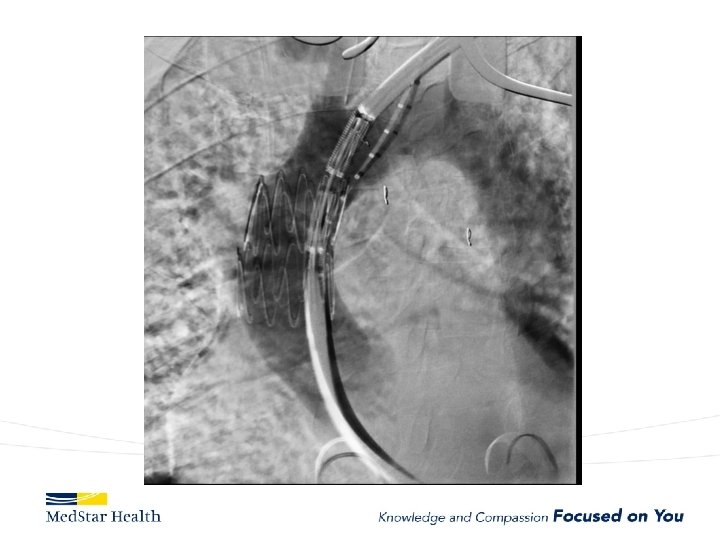

ARCH

Medtronic Mona Lisa

Bolton

Thoraco